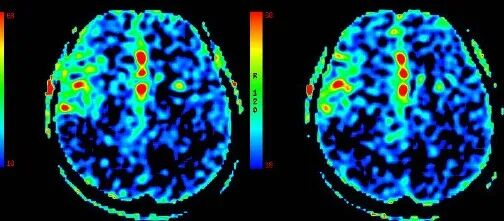

ASL

重要影像结论:3月前ASL示:左侧额颞顶枕叶、右侧颞枕叶血流灌注量明显减低。

重要影像结论:ASL示:原左侧额颞顶枕叶、右侧颞枕顶叶血流灌注量明显减低区范围较3月前明显增大。